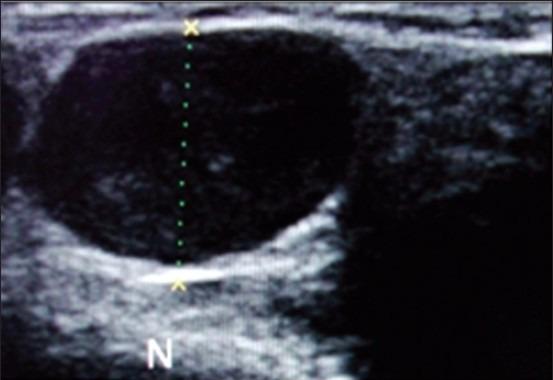

The objective of this study was to assess nodal vascularity by Doppler sonography and to find out the correlation between clinical and various Doppler sonographic features for the detection of the metastatic nodes in oral cancer patients.

A total number of 55 patients of histopathologically proven oral cancer presenting with enlarged superficial cervicofacial lymph nodes were included in the study. Patients were subjected to clinical examination according to a specially designed proforma and the TNM staging was done. If more than one enlarged nodes were present, then the node with the largest diameter was chosen for further Doppler ultrasonographic examination followed by fine needle aspiration cytology test of the same node.

Correlations of patterns of color Doppler flow signals with cytological diagnosis showed that central type of vascular pattern was statistically significant parameter for benign lymph nodes and peripheral type of vascularity was highly significant parameter for malignant lymphadenopathy. It was found that the cut-off value of resistive index 0.6 was statistically significant in the assessment of metastatic node (P < 0.01) with a sensitivity of 45.5% and specificity of 93.9%. On comparison of the clinical features (TNM staging) with Doppler sonographic features, it was found that the characteristic features suggestive of malignant lymph nodes on Doppler sonography such as peripheral blood flow and high resistive index were more consistently and frequently associated with the higher sub-stages of T3 and T4 and N2b and N2c of TNM staging system.

Nodal vascularity may be used to differentiate benign from malignant lymphadenopathy. Proper judicious use of non-invasive color Doppler ultrasonographic examination provides an opportunity to eliminate the need for biopsy in reactive nodes and provide treatment in a more precise manner.